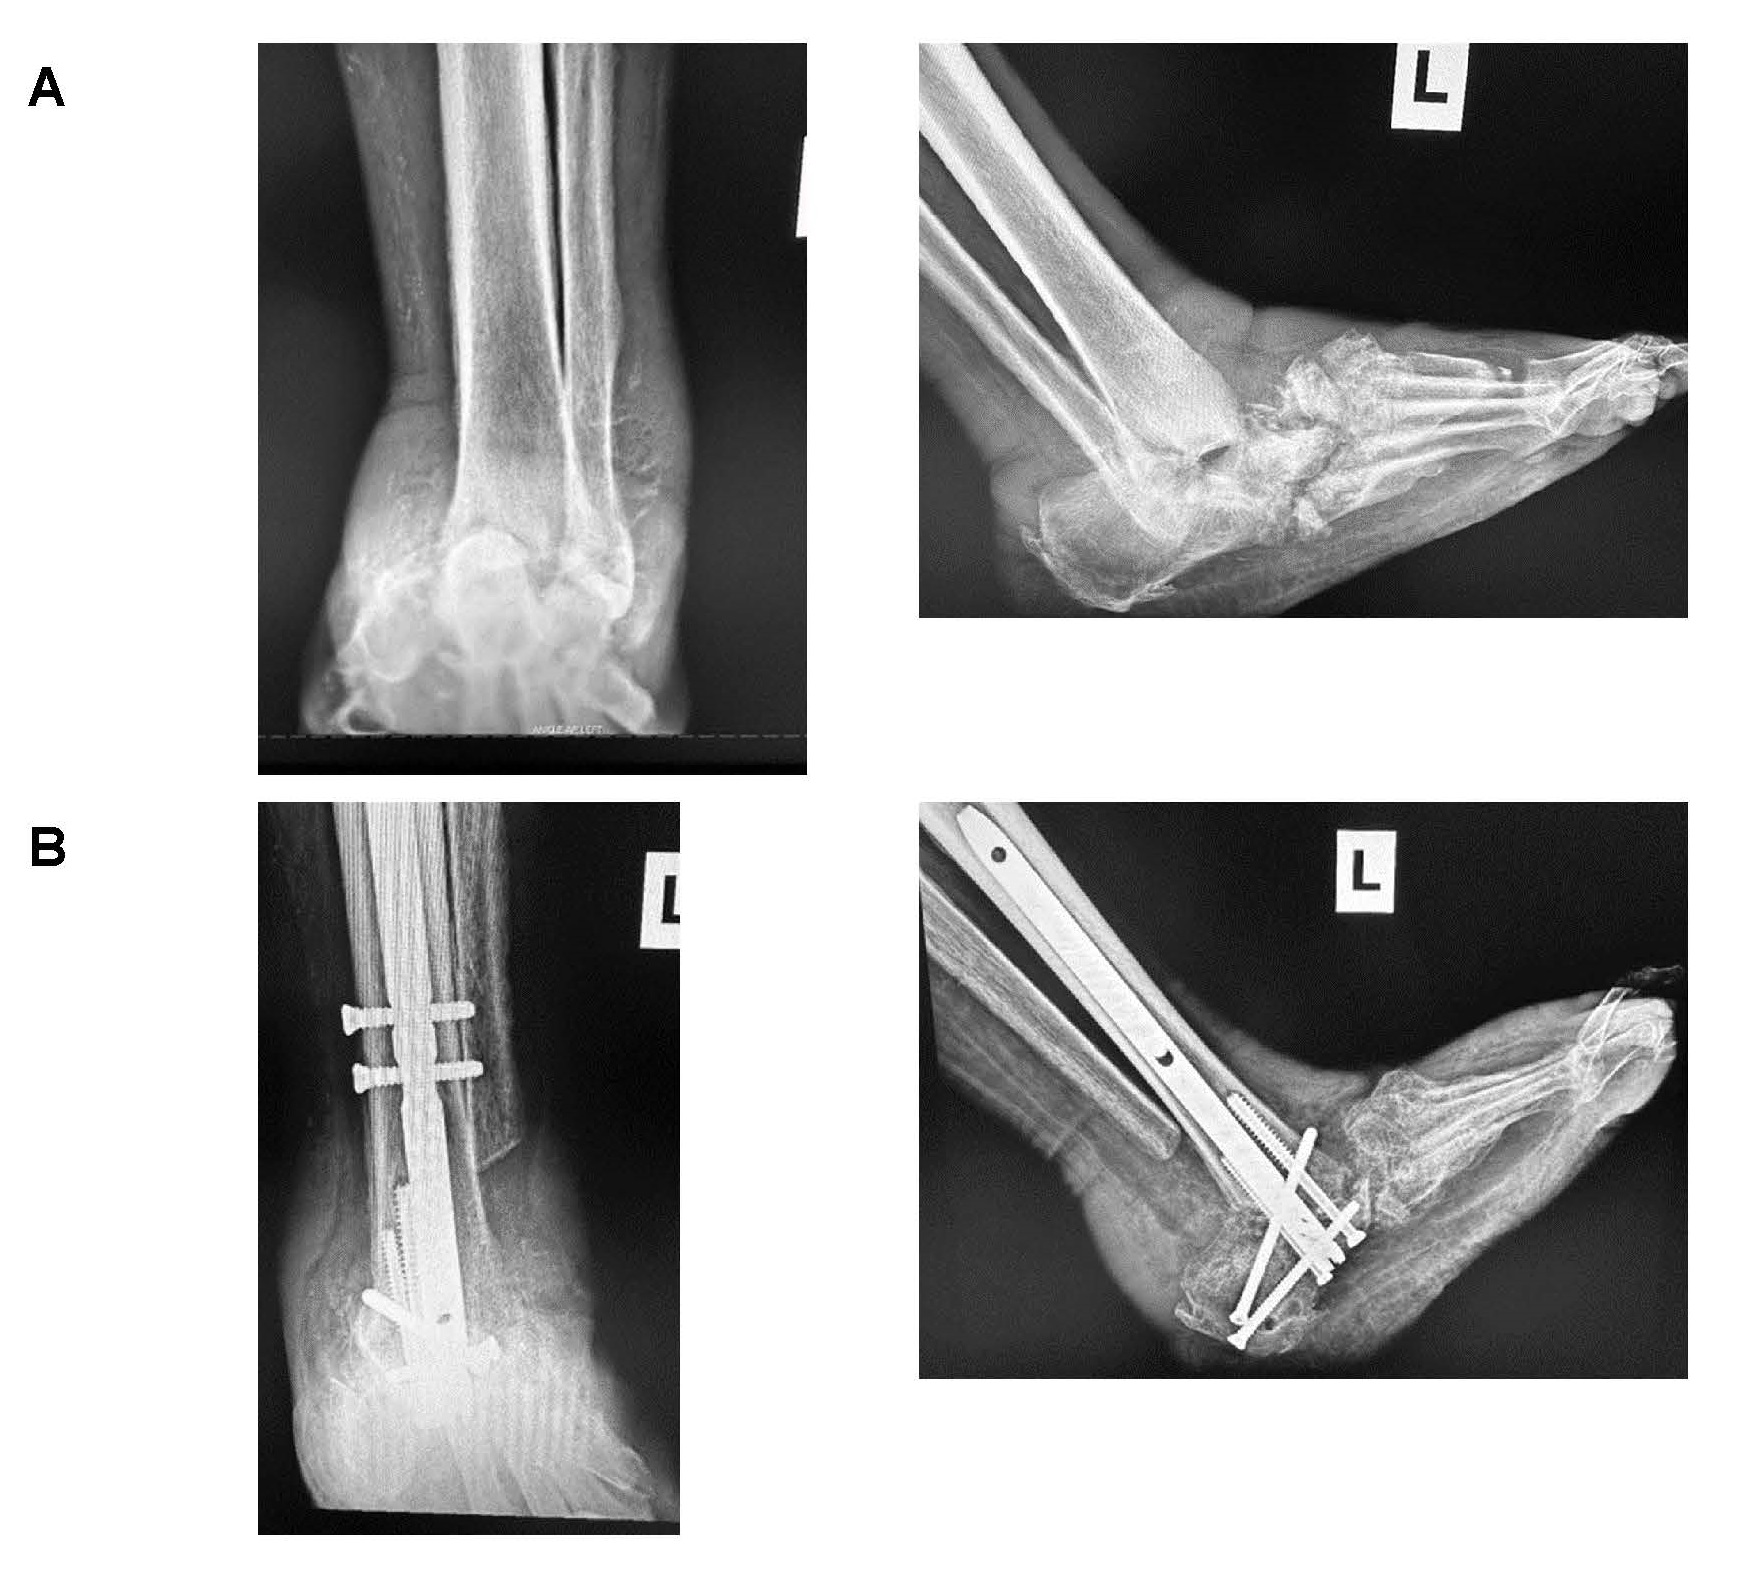

Patients who participated in the study presented with unstable foot and/or ankle deformities developed from CN. After standard foot and ankle radiographs were obtained along with advanced imaging studies (Magnetic Resonance imaging and/or Computed Tomography (CT) scans), if needed, along with a clinical evaluation, patients discussed their treatment options before electing to undergo a surgical reconstruction to realign and stabilize the deformity. The standard surgical procedure had the patient placed in a supine position on the operating table under general or spinal anesthesia along with the use of a thigh tourniquet. Patients had standard joint prep at the affected joints with curettage, rotatory burring along osteotomies as needed to realign the deformity. Patients who had tarsometatarsal and navicular-cuneiform joint deformities with no ankle instability or severe equinus deformity underwent a midfoot reconstruction that included midfoot osteotomy with realignment, medial and lateral column fusion, and subtalar joint fusion with the use of either beams, bolts, and/or a midfoot nail device with the use of bone grafting substitute to help promote healing at the fusion sites (Figure 1). Ankle reconstruction was indicated for patients with 1) a plantarflexed talus along with disassociation of the talus and the calcaneus with the calcaneus posteriorly disassociation of the subtalar joint, 2) the destruction of the navicular and/or dislocation of the midtarsal joints on top of the navicular, or 3) if there was gross instability of the ankle and/or subtalar joint or destruction of the bone within the ankle joint. Ankle reconstruction was performed when destruction of the talus bone or a varus/valgus deformity of the ankle joint upon stance was seen in the imaging. Ankle reconstruction was fixated with a hindfoot fusion nail and bone grafting material to promote fusion at the site (Figure 2). An external fixator was used in most patients (n = 26) to help maintain the correction and provide stability when healing. Patients without external fixation were placed in a below the knee cast. All patients stayed overnight in the hospital following surgery. Patients were seen in the office every 2 weeks for follow up, and radiographs were obtained to assess healing and patient compliance to remain non-weightbearing on the affected limb. CT scans were obtained 12-16 weeks post-operatively to assess healing at the fusion sites [21]; external fixation, if used, was removed at this time. All patients went into a CROW boot until the 1-year follow-up date.

Figure 2: A) Pre-operative vs. B) 1-year post-operative radiographs showing an ankle Charcot reconstruction with ankle fusion using a hindfoot fusion nail. View Figure 2